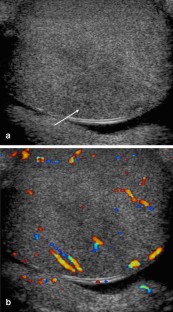

Fig. 1